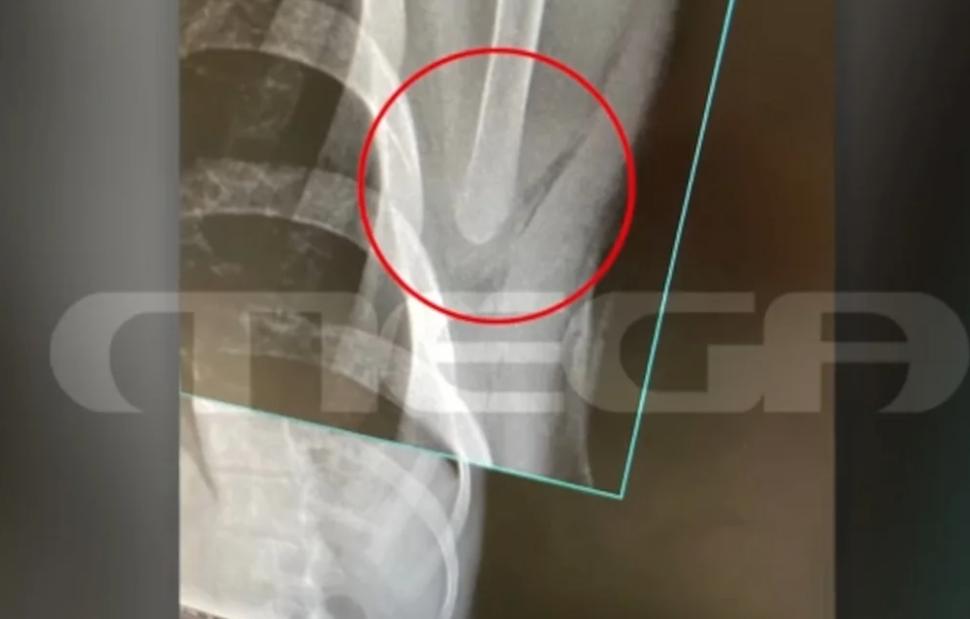

Οι δράστες στη συνέχεια έβγαλαν τα κατσαβίδια και ένας εξ αυτών κάρφωσε τον νεαρό στην πλάτη. Το τραύμα του ήταν βαθύ, όπως αποτυπώνεται και στην ακτινογραφία του θύματος της επίθεσης, που απείλησε ζωτικά του όργανα.